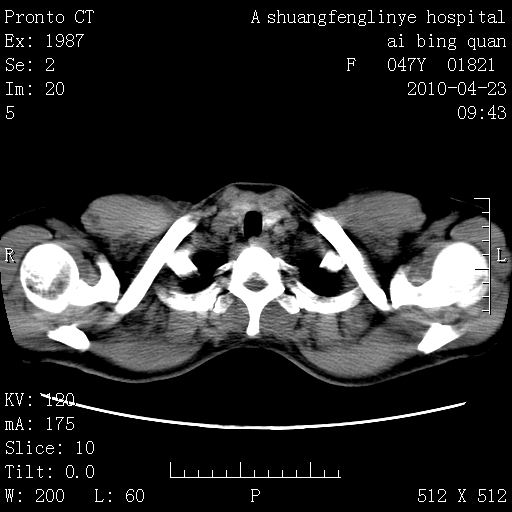

标题: CT25944:胸痛、气短、前几日高烧!肺Ca?请会诊! [打印本页]

标题: CT25944:胸痛、气短、前几日高烧!肺Ca?请会诊!

左侧乳腺低密度灶